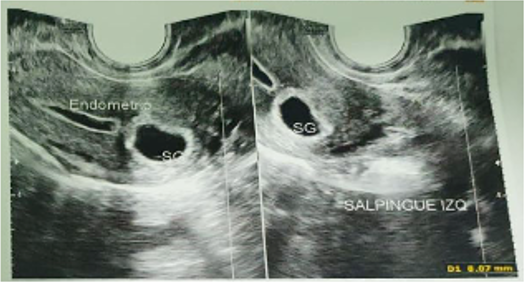

Figure1: Transvaginal ultrasound at 5 months after treatment with methotrexate continued to report the presence of a gestational sac in the cornual region

However, during the five-month follow-up, β-hCG never became negative and transvaginal ultrasound reports continued to report the presence of a gestational sac in the left cornual region. Notably, one month after methotrexate administration, the patient resumed regular menstrual bleeding of normal volume (Table 1: Record of the evolution of the β-hCG in the follow-up carried out at five months).